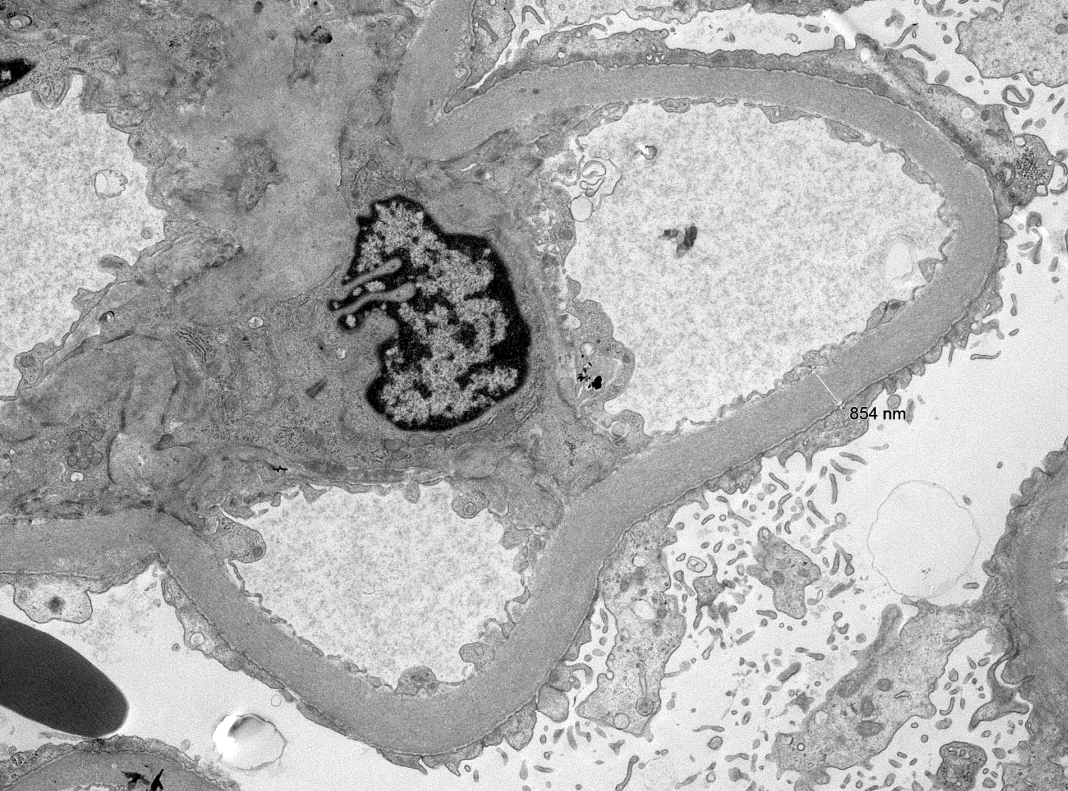

"The Banff 2024 Kidney Meeting Report: Rejection as a spectrum of phenotypes and focus on differential diagnostic reasoning," Naesens et al.